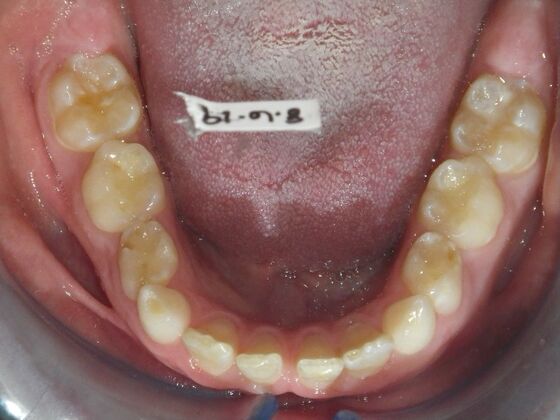

Orthodontic treatment in Phases: Case 12

This patient does not like his anterior deep bite and the flaring of the right lateral incisor as well as anterior spacing. The solution was to correct his Class II molar relationship, Division II and deep anterior bite and close spacing as much as possible with addition of composite restorations on distals of lateral incisors. We began with utility archwires, eventually correcting Class II molar with distalizing appliance, and continued with final tip and torque. All that is left now is to ad composite to distals of upper lateral incisors.